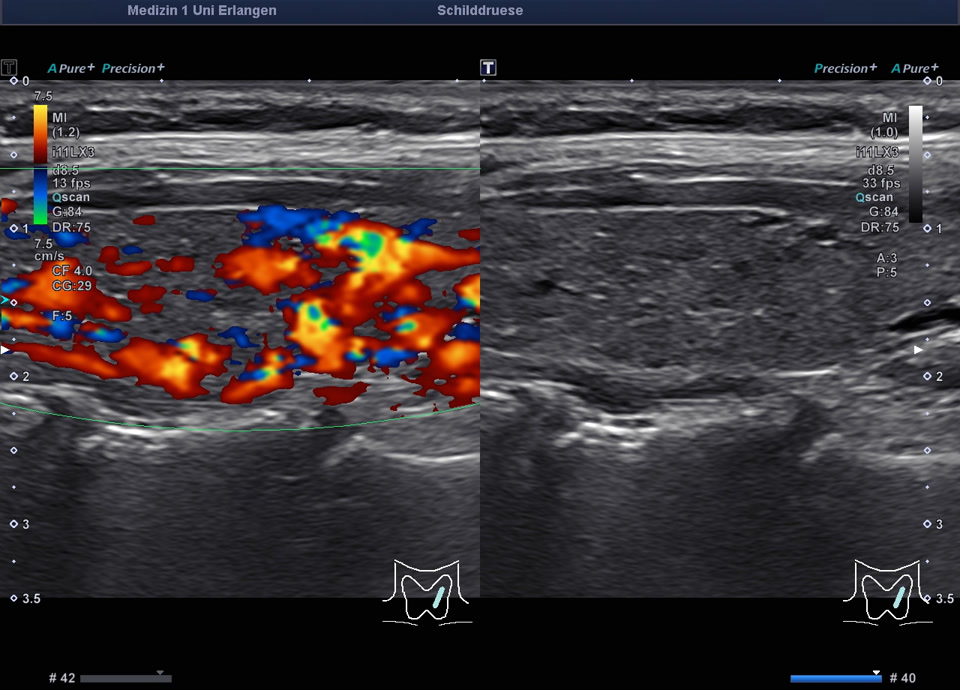

36-jähriger Patient mit Tremor, Tachykardie, Exophthalmus und Gewichtsverlust. Sonographisch stellt sich die Schilddrüse beidseits mit echoarmer inhomogener Parenchymstruktur dar. Gesamtvolumen 20,5 ml. Farbdopplersonographisch hypervaskularisiert. Laborbefunde: basales TSH erniedrigt, T3/fT4 erhöht, TRAK positiv. Befundkonstellation vereinbar mit M. Basedow. Unter Therapie mit Thiamazol und Propranolol beschwerdefrei. Bei Verlaufskontrolle zwei Jahre später sonographisch echoreiches minimal inhomogenes Parenchym bei normalem Volumen (15 ml).